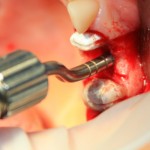

Закрытый (вертикальный) синуслифтинг производится через уже подготовленную лунку импланта с помощью специальных инструментов — остеотомов-остеоконденсоров (рис 6).

Существующий «баллонный» синуслифтинг также является закрытым. Как следует из названия, при проведении вертикального синуслифтинга отсутствует контроль над состоянием слизистой оболочки гайморовой пазухи, поскольку увидеть ее через лунку импланта диаметром, к примеру, 3,4 мм без специального оборудования нельзя (рис 7, 8).

Рисунок 7, 8. Проведение закрытого синуслифтинга с помощью остеотомов-остеоконденсоров.